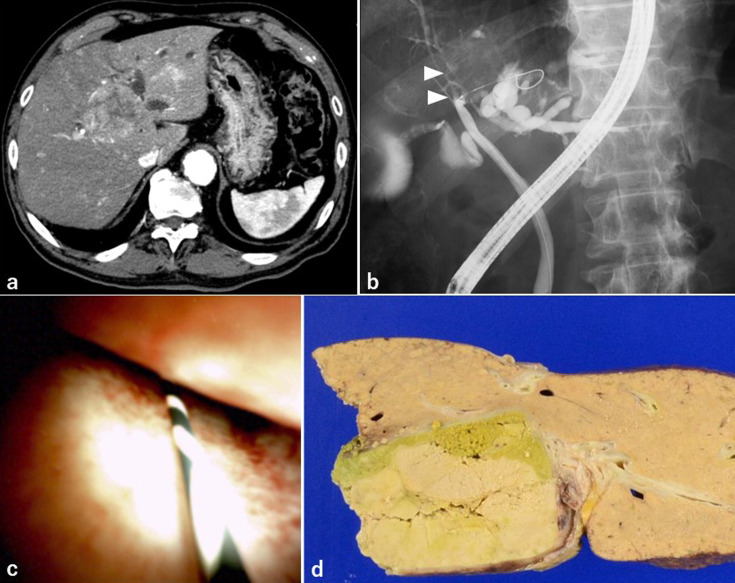

Objective: Bile duct tumor thrombosis in hepatocellular carcinoma (HCC) is a relatively rare event with a poor prognosis. Furthermore, bile duct tumor thrombus in HCC may be misdiagnosed when only imaging modalities are used. The efficiency of peroral cholangioscopy (POCS) in evaluating bile duct lesions has been reported. Patients: We present three cases of HCC with bile duct strictures in which POCS was performed as a preoperative evaluation. Results: In these three cases, diagnosing whether the lesion was a bile duct tumor thrombus on CT and endoscopic retrograde cholangiopancreatography was difficult. We performed POCS in three cases and were able to diagnose the presence of bile duct tumor thrombus of HCC, including differentiation from extrinsic compression of the bile duct. Conclusion: POCS for HCC with bile duct features is useful for the preoperative diagnosis of bile duct tumor thrombus, especially in cases where the surgical procedure depends on the presence of bile duct tumor thrombus.

Abstract Image